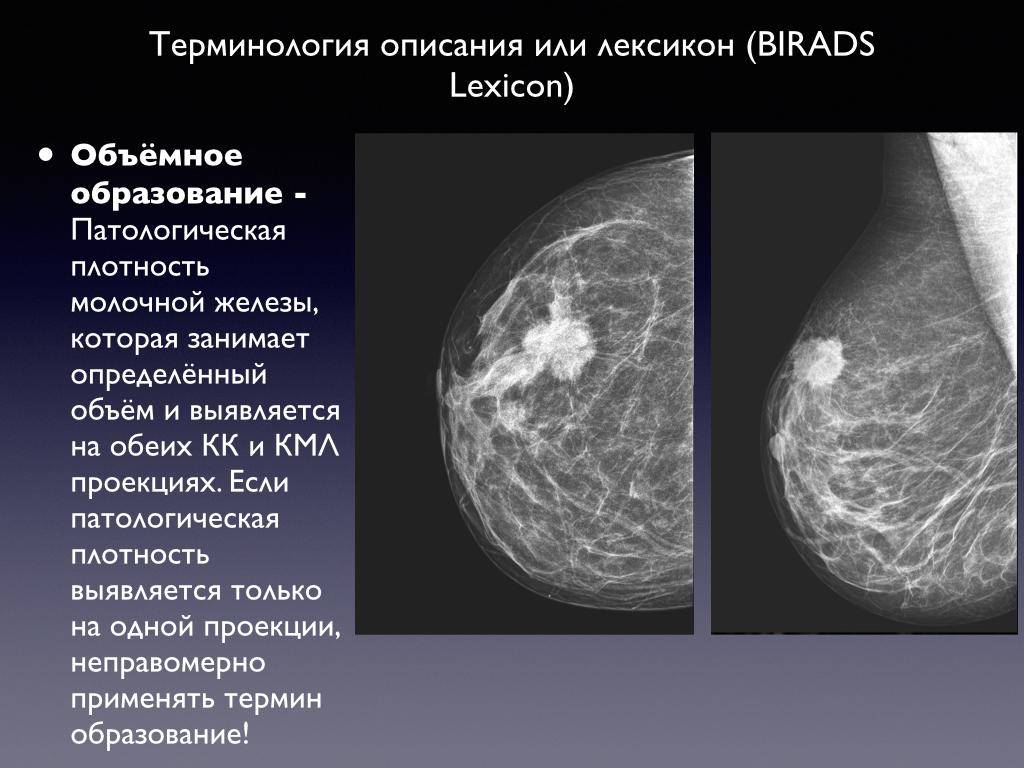

Что такое маммография: важность, процесс и результаты

Раздел: Необычные решения